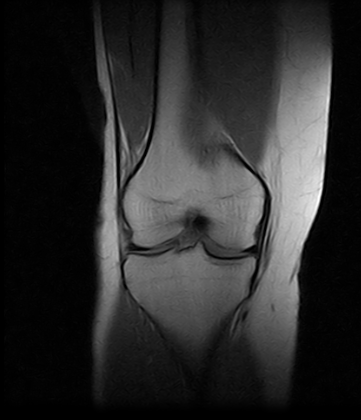

Ressonâncias Magnéticas Joelho

Se você pesquisa ressonâncias magnéticas joelho com eficiência e profissionalismo, não deixe de vir conhecer os serviços oferecidos pela RM Brasil.